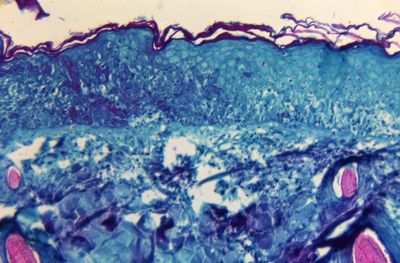

Symptoms of monkeypox are also similar to (albeit milder than) smallpox. Patients experience fever, intense headache, swelling of the lymph nodes, back pain, achy muscles, extreme tiredness, and skin lesions. It can, however, it can also cause severe illness that requires hospitalization. The fatality rate is 3 to 6 percent.